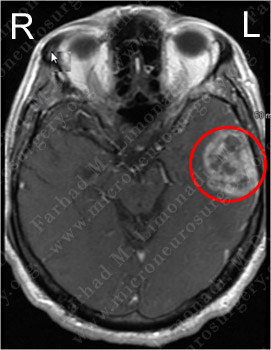

Imaging

MRI scan of the patient's brain showed a left temporal brain tumor.